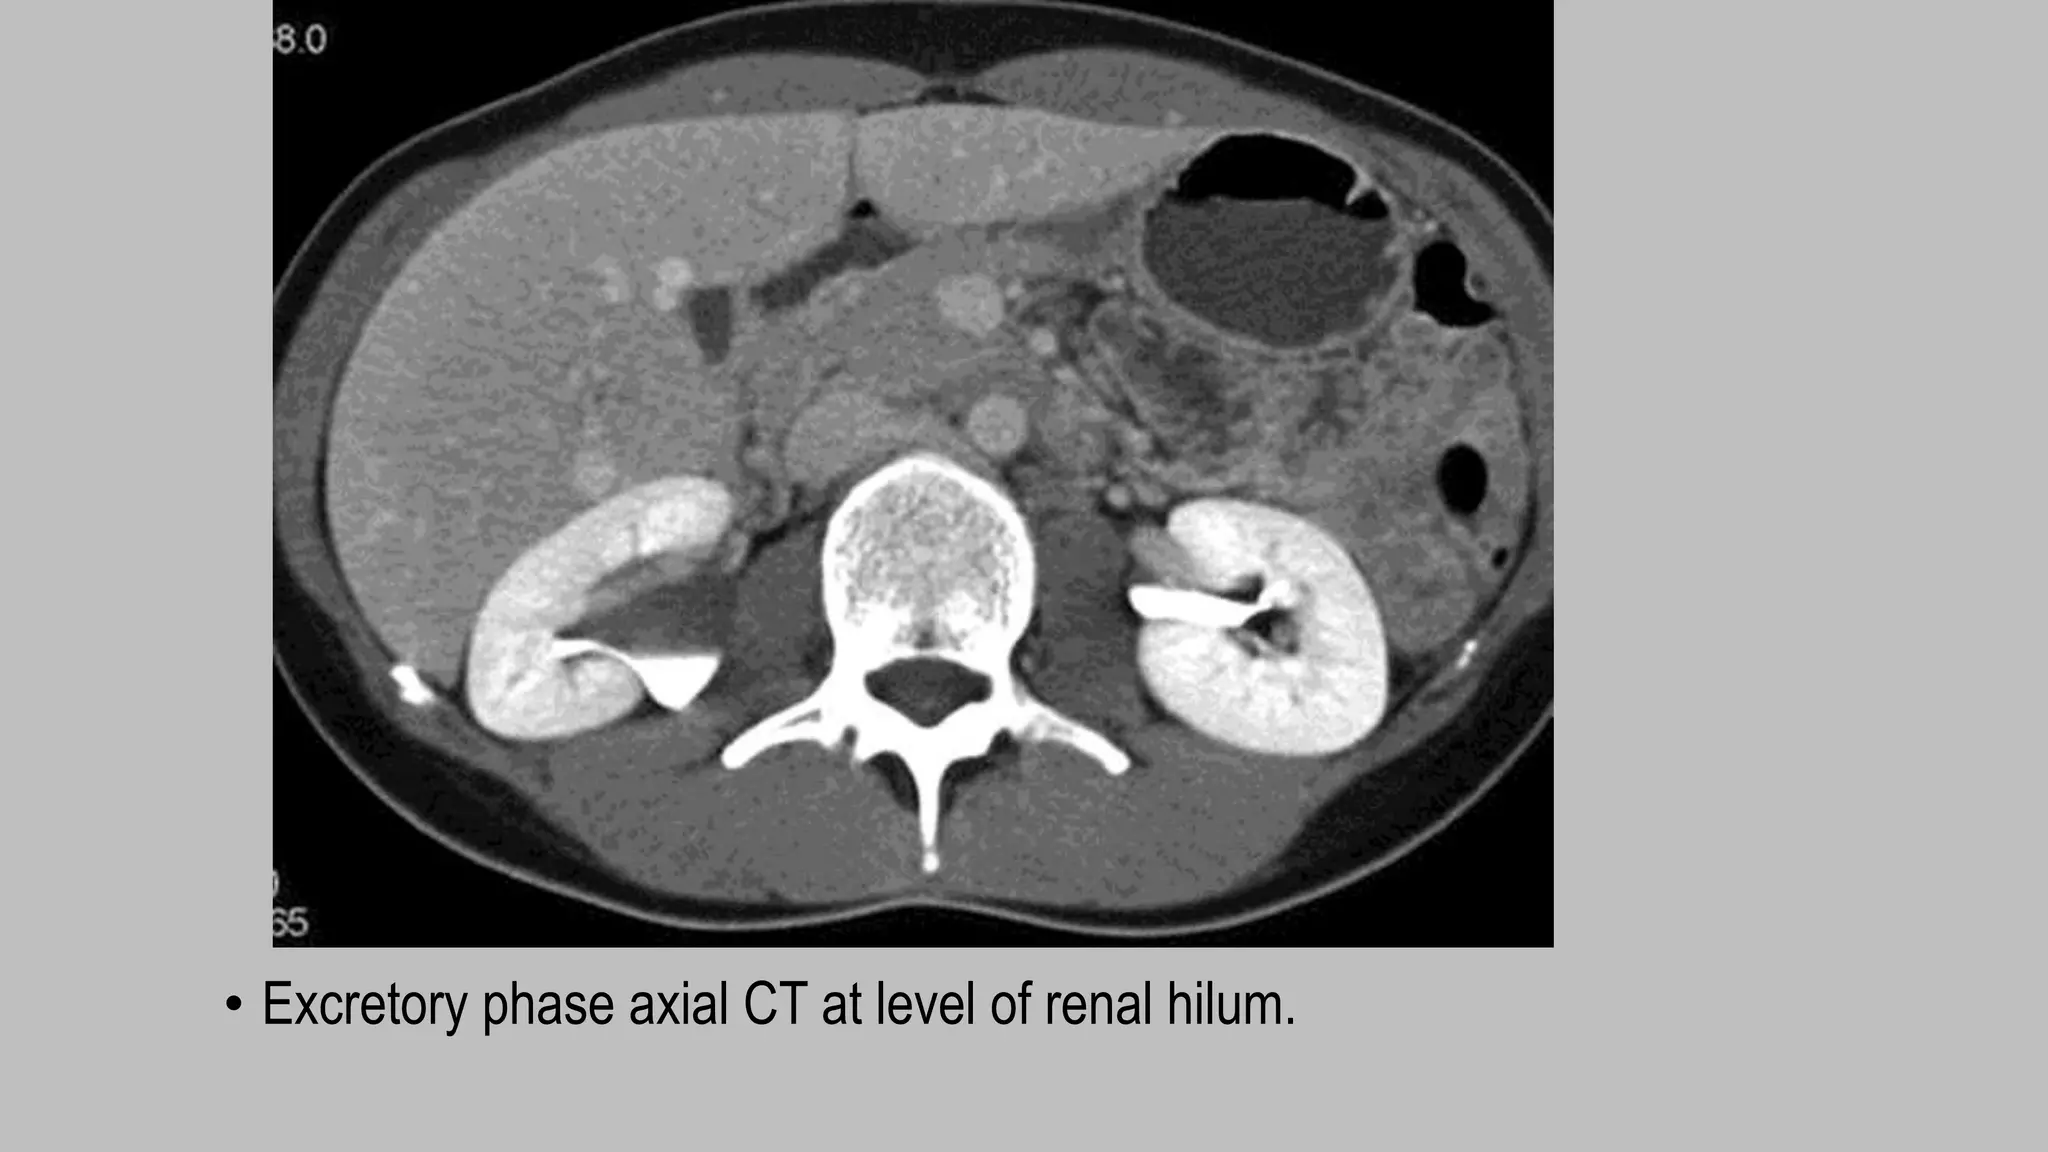

Excretory phase

• Begins approx 5-8 min after the start of contrast injection.

• The contrast excretes into the collecting system decreasing the attenuation of the

nephrogram

• helpful to better delineate the relationship of a centrally located mass with the

collecting system.

• also useful for evaluating urothelial masses.

• McNicholas et al (28) showed that excretory phase CT scans obtained with

patients in a prone position also improved opacification of the distal ureters

compared to CT scans obtained in supine patients without abdominal compression.

• Excretory phase axial CT at level of renal hilum.

• CT urogram: Excretory phase obtained 7 minutes following

contrast administration. This phase is used to look for filling

defects in the urinary collecting system.